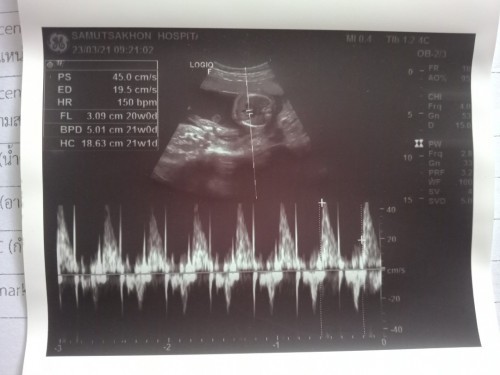

ผช.ครับ

ชายค่ะ

ผช.ค่ะ